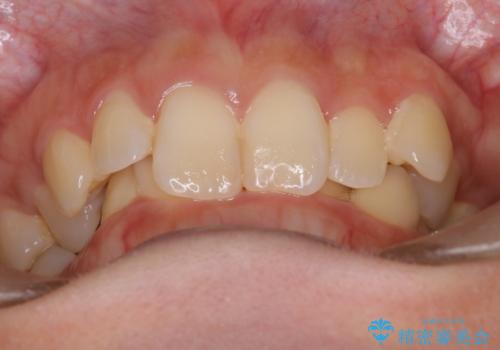

ディープバイト改善のためのインビザライン治療

- 患者様は、全体的な歯列のガタガタとディープバイト(深い噛み合わせ)を主訴として来院されました。診断の結果、ディープバイトを改善するためには、歯列全体の拡大が必要であると判断しました。治療には、透明なマウスピース型矯正装置「インビザライン」を使用し、歯を適切に拡大しながら歯並びを整える計画を立てました。治療期間はおおよそ2年を見込んで進め、最終的に見た目にも大きく変化をもたらすことを目指しました。

ディープバイトの治療には、奥歯の高さや前歯の位置に対する繊細な調整が必要です。本症例では、インビザラインによる歯列拡大を行うことで、噛み合わせを改善し、歯並び全体を整えました。治療過程では、歯間のスペースを確保するため、IPR(インタープロキシマルリダクション)を適宜行い、無理なく歯列の調整を行いました。治療後は、歯並びが大きく改善され、患者様の見た目にも大きな変化が現れました。インビザラインは透明で目立たず、治療中の見た目を気にされる患者様にも配慮した治療法です。